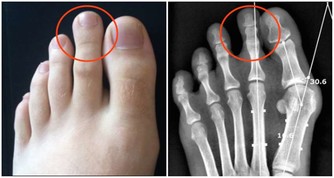

濕氣重對身體有什麼危害呢?

中醫稱濕氣為邪濕,現在濕氣已經是我們所有的人通病了,

大部分人身體都有濕氣,濕氣剛剛侵入你的身體時你會常感到四肢無力,頭昏沉,總睡不夠,

這些你不去注意,時間就了濕氣就會引發出一些大毛病比如:

如:高血壓、哮喘、脂肪肝、心腦血管等疾。

濕氣久而不治,就會嚴重加深一些疾病的病情,再去治療的話就會難上加難,吃飯打針都難以至效,治什麼病都是事倍功半,這正是很多慢性疾病的根源所在。